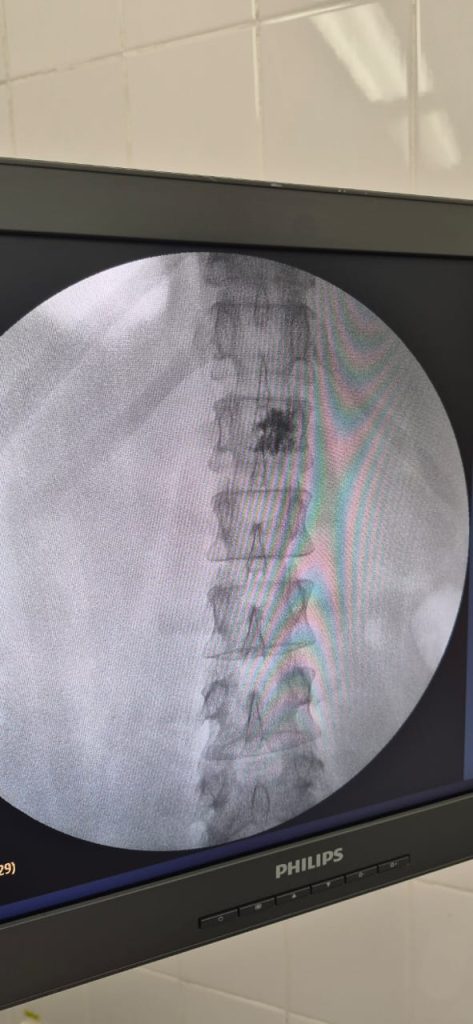

К счастью, сегодня есть современный и безопасный метод лечения — перкутанная вертебропластика. Это малоинвазивная процедура через маленький прокол, при которой в ослабленный позвонок вводится специальный медицинский цемент. Он укрепляет повреждённый участок, останавливает рост гемангиомы и быстро снимает боль. Операция длится около 20–30 минут, проводится без общего наркоза, а вставать можно уже через пару часов.

В Городской многопрофильной больнице Тараза такие операции выполняются ежедневно опытными нейрохирургами на современном оборудовании. Важно, что вертебропластика доступна по ОСМС, то есть бесплатно для пациента при наличии медицинских показаний. Если на МРТ вам выявили гемангиому или появились боли в спине, лучше не откладывать визит к специалисту. Своевременное обследование и лечение позволяют избежать опасных осложнений и сохранить качество жизни.